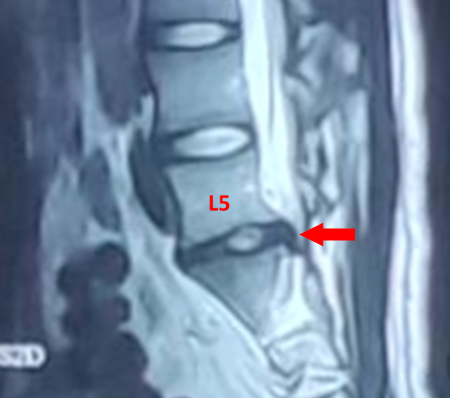

红色箭头:突出的L5/S1椎间盘

在家人的陪同下,小祁来到附近医院就诊,经腰椎磁共振检测发现,小祁腰5/骶1椎间盘左后突出。看到这个结果,小祁心里咯噔一下:腰椎间盘突出症不是中老年人才会“中枪”的吗?为什么我这么年轻就腰椎间盘突出了?以后我还能继续打篮球、跑步,正常运动吗?